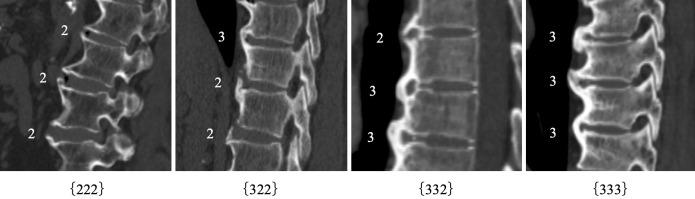

Of the 188 patients, 37 (19.7%) and 48 (25.5%) were diagnosed with DISH on the first and second CT scans, respectively. Pre-DISH was defined as the ossification characterized by the modified Mata score of three contiguous intervertebral spaces with a score of ≥2 points (222; 2 points, ligament ossification of half or more of the intervertebral disc height but incomplete fusion), and 52 patients were diagnosed with pre-DISH. Of the 52 patients with a score of ≥(222), 11 (21.2%) were diagnosed with DISH 5 years later.

Patients who have three contiguous intervertebral spaces with a modified Mata score of 2 or 3 points should be considered pre-DISH.

188例患者中,首次和第二次CT扫描时分别有37例(19.7%)和48例(25.5%)被诊断为DISH。Pre-DISH被定义为三个连续椎间隙的改良Mata评分为≥2分(222;2分,椎间盘高度一半或更多的韧带骨化但未完全融合)的骨化,52例患者被诊断为pre-DISH。在52例评分为≥(222)的患者中,11例(21.2%)在5年后被诊断为DISH。

三个连续椎间隙的改良Mata评分为2分或3分的患者应被视为pre-DISH。